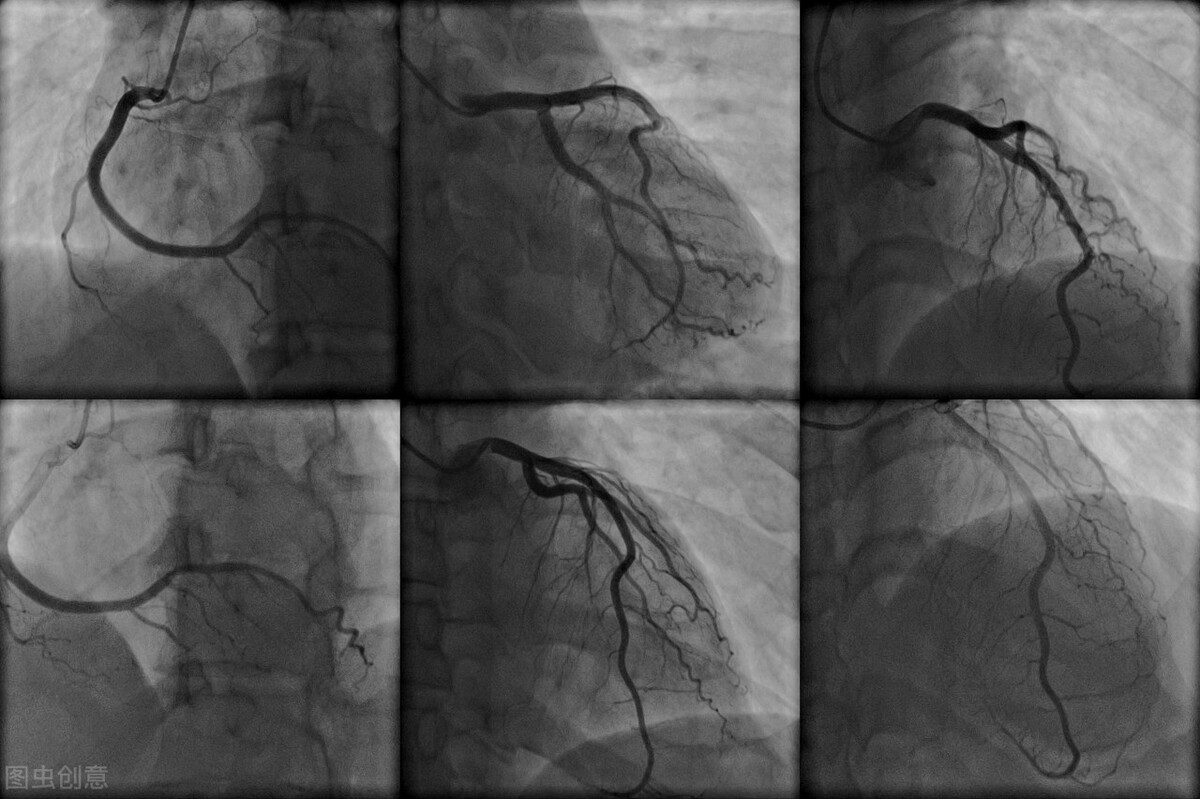

二、狭窄程度和比例是怎么来的?

我们经常说冠脉造影是诊断冠心病的“金标准”,也就是诊断冠心病最准确的一种检查方法。可是即使是“金标准”,这个狭窄程度,也是我们通过X线照射,通过体内造影剂显影,投影在显示屏上。介入医生根据显示屏上的影响,结合自己的经验,通过肉眼来判断心脏血管的狭窄程度。

这种观察心血管狭窄程度的方法,一方面是肉眼本身存在一定的误差,比如张医生看是70%的狭窄,李医生看是75%的狭窄,王医生看是80%的狭窄。当然大部分情况下有经验的医生看到的狭窄程度是一样的。

另一方面造影是X线照射,并不是立体地看到血管内部,显示屏显示的血管图像也是平面的,对于血管拐弯的地方,可能就会看得不清楚,把轻度的看成重度,把重度看成轻度的。

当然,对于轻度狭窄或很严重的狭窄,一般不会有这么大误差,一般小于70%的狭窄,大家会公认是不要支架治疗,对于大于80%的狭窄大家公认需要支架治疗。

但对于70-80%的狭窄,可能误差就比较大,争议比较多,就像陈师傅这样的狭窄。